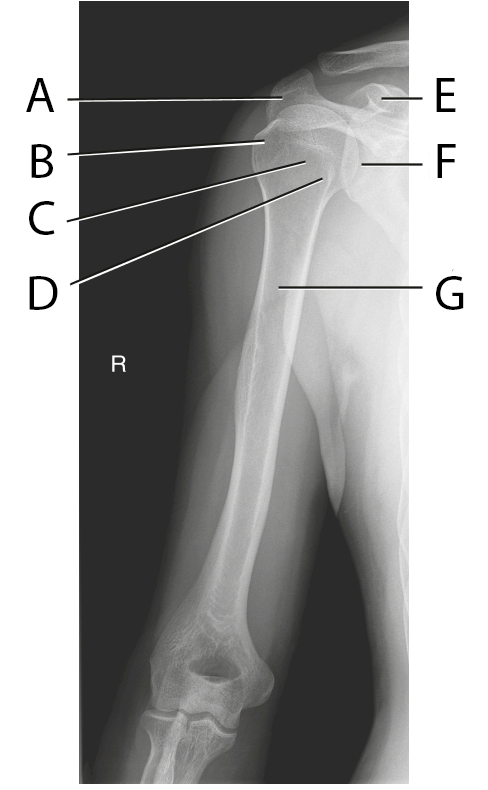

Identify A from this AP Humerus Projection

Acromion

Identify B from this AP Humerus Projection

Greater Tubercle

Identify C from this AP Humerus Projection

Head of Humerus

Identify D from this AP Humerus Projection

Lesster Tubercle

Identify E from this AP Humerus Projection

Coracoid Process

Identify F from this AP Humerus Projection

Scaphulohumeral Joint

Identify G from this AP Humerus Projection

Proximal Humerus